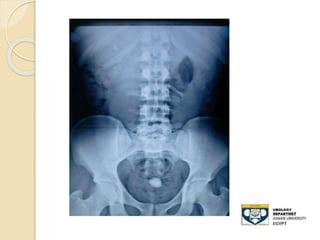

KUB film

 - Advantages:

◦ 80-90% of stones are radio-opaque

◦ Minimal radiation

 Disadvantages:

◦ Radiolucent stone

◦ Easy to miss mid-ureteral stones over the

sacrum

◦ Bowel gas can obscure its efficacy

◦ Cannot differentiate , Stones,Calcified LN

,

◦ Sensitivity: 50-70%